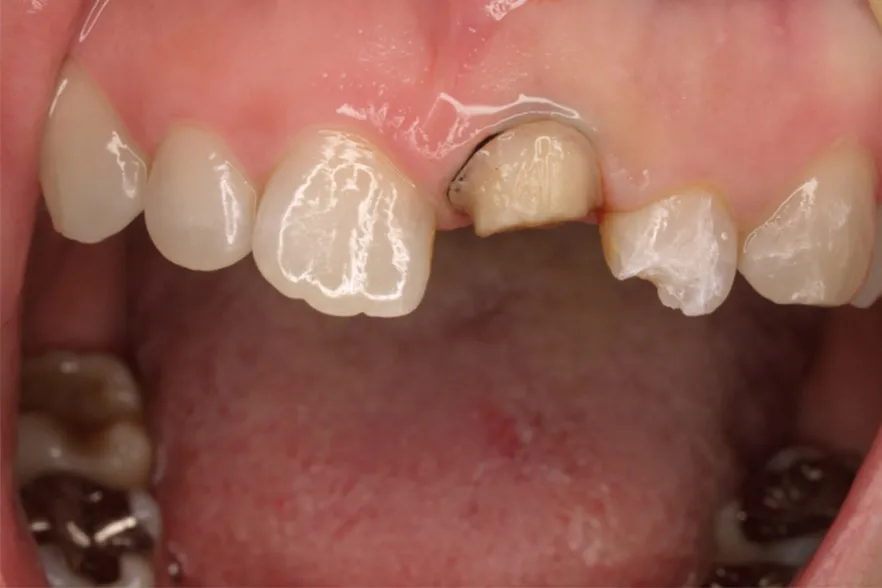

case1

Before

After

施術内容 | 口腔内診査〜カウンセリング 歯周初期治療 仮歯を入れ機能的な評価 最終的な型取り〜装着 |

---|---|

治療期間 | 2ヶ月 |

治療回数 | 6回 |

リスク | クリーニングにこない場合歯茎が下がってくるため今後のメンテナンスが必須となる |

費用(税込) | 約¥341,000 |